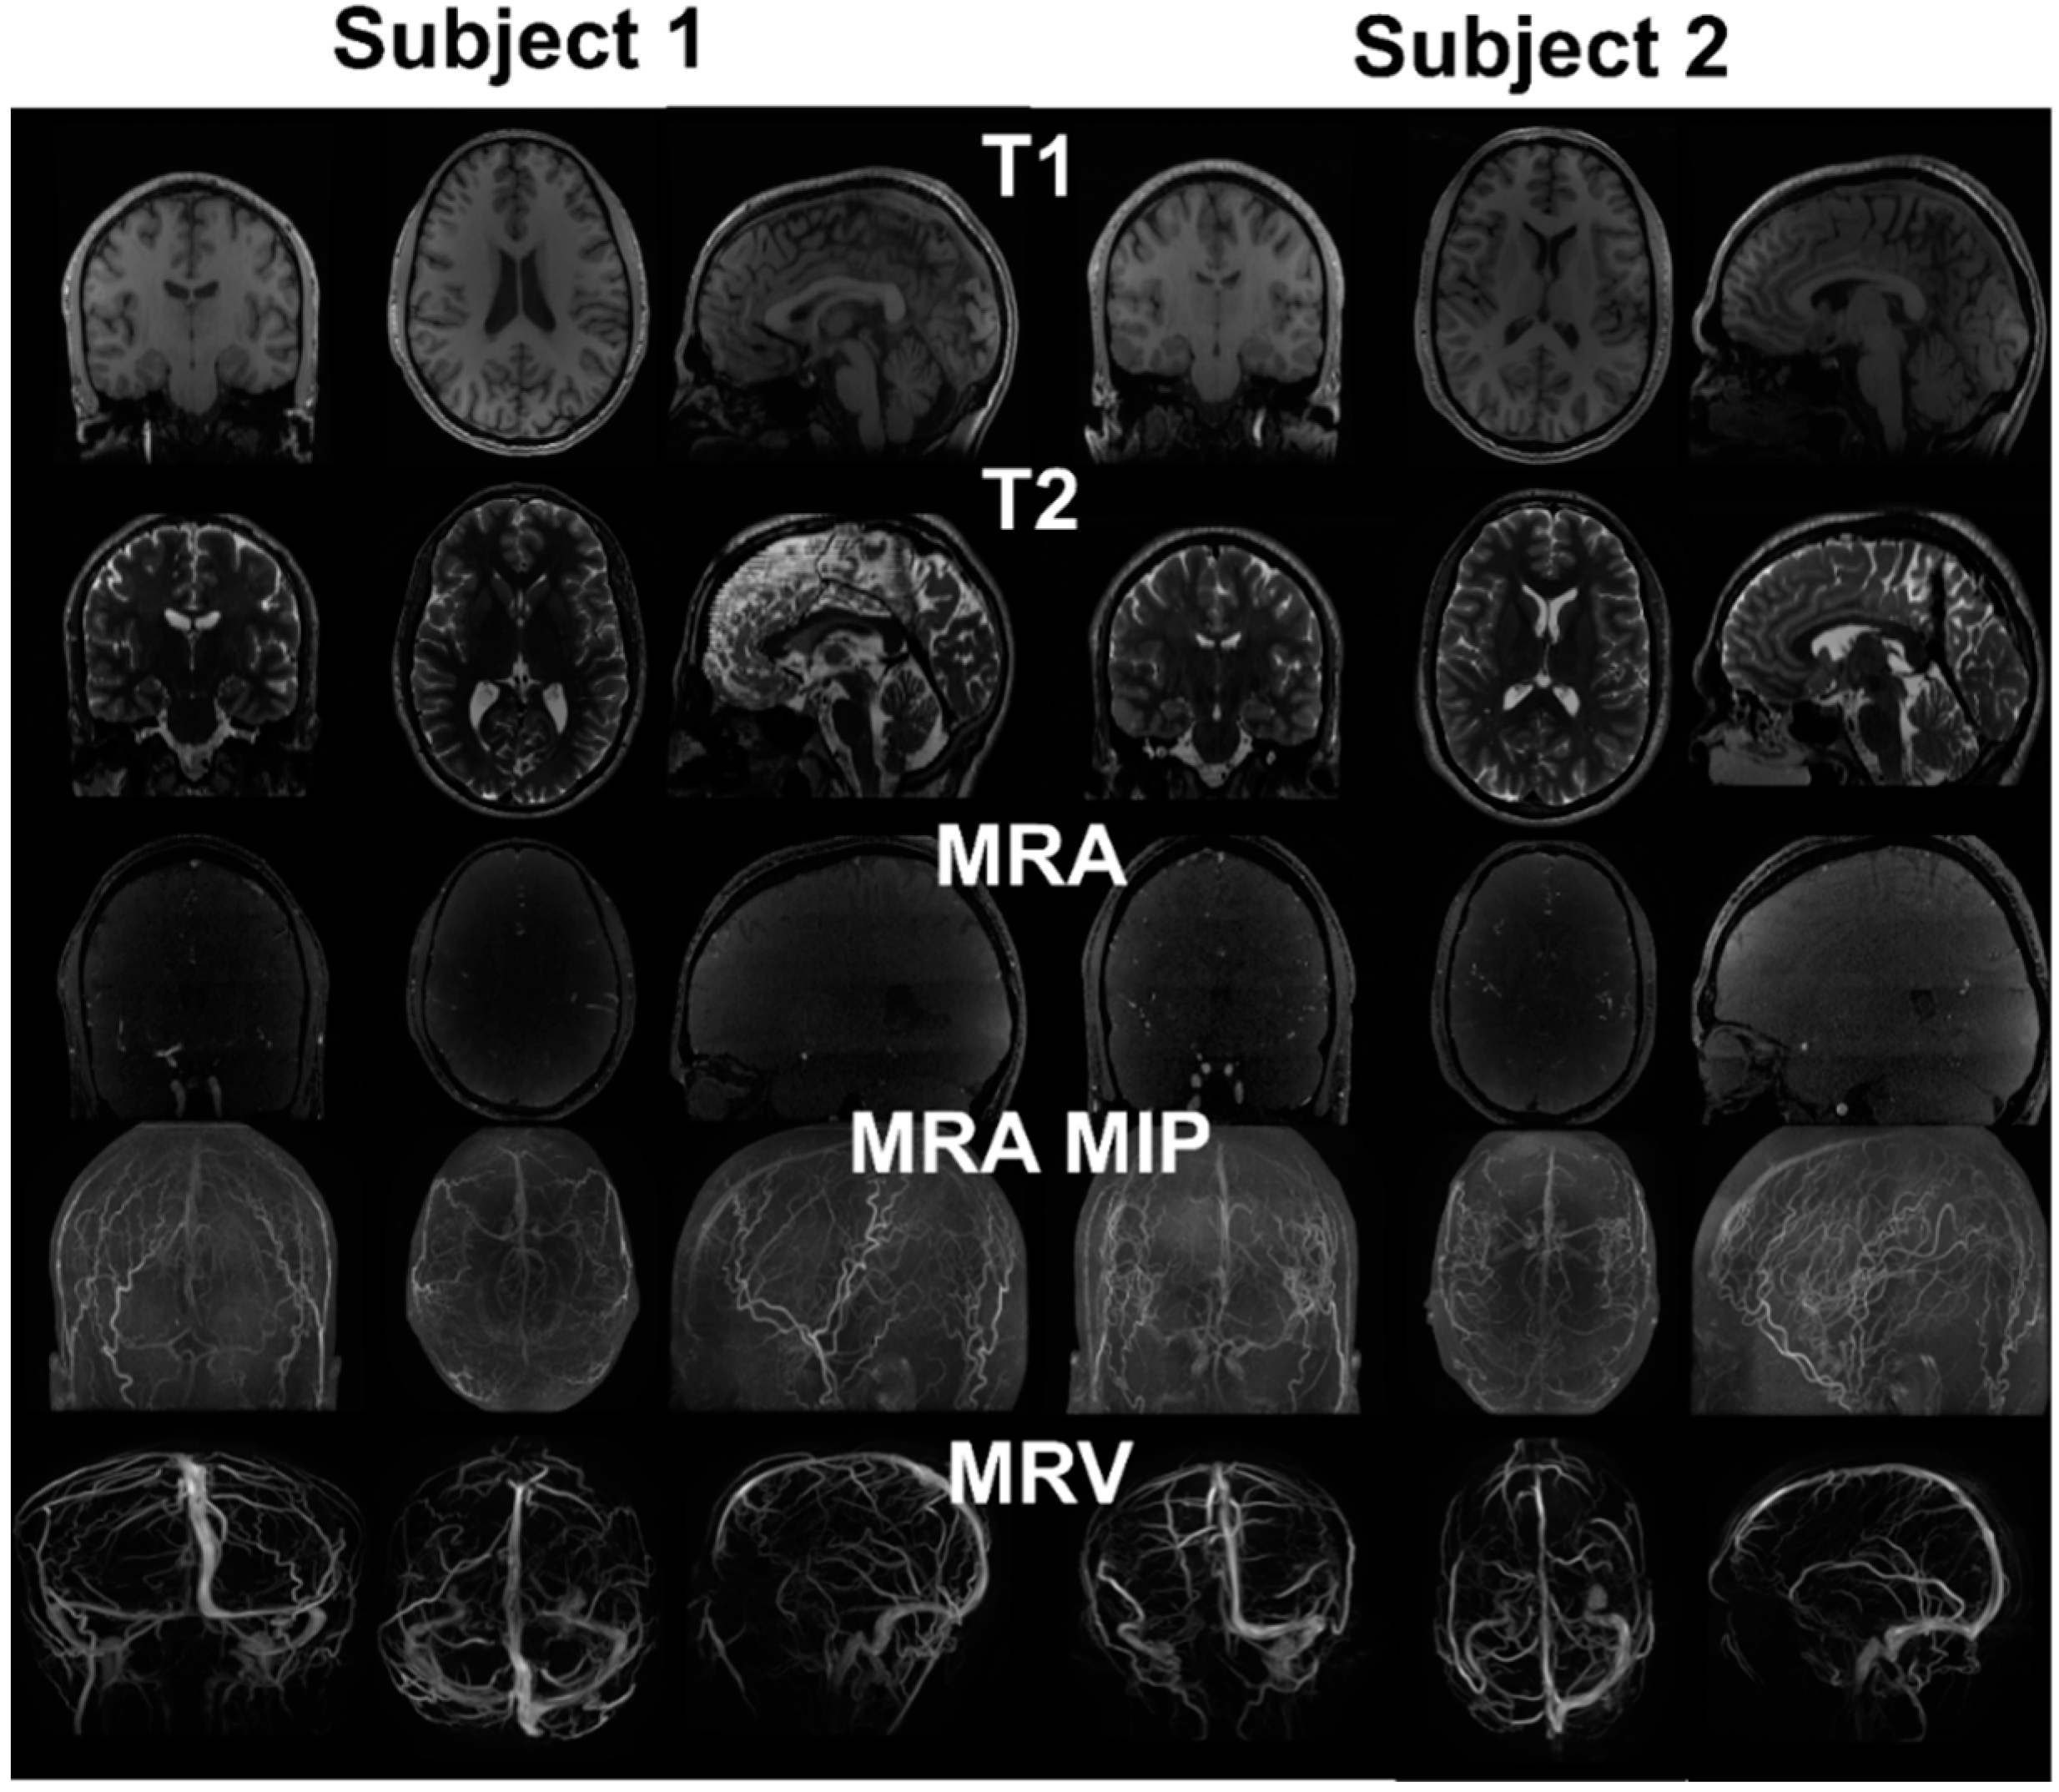

Figure 2 exhibits the MR imaging studies from both subjects in axial, sagittal and coronal views respectively. The maximum intensity projection is used for the MRA to better delineate the vessels. The imaging protocols inherently brighten grey and white matter in T1, cerebrospinal fluid space in T2, arteries in MRA, and veins in MRV. The scalp exhibits high intensity in both T1 and T2. The skull does not exhibit any signal in all imaging studies. Image registration was performed to compensate for the different resolution and slice settings in each imaging protocol. Figure 3 shows the registered and segmented results with red being arteries, dark blue being veins, dark grey for grey matter, light grey for white matter, light blue for cerebrospinal fluid space, white for skull, and flesh color for scalp. Figure 3 shows that the coregistration successfully aligned the different structures together.

Figure 2.

MRI images from two healthy subjects. T1 provides distinction of grey and white matter, skull and scalp. T2 provides cerebrospinal fluid space and contrast between gray and white matter. MRA enhances the intensity of vessels using flow phenomenon. The maximum intensity projection (MIP) provides better distinction of vasculature compared to the raw image. Due to the pulse sequence design, the brain tissue was removed from the MRV, showing only the signals from the vein.